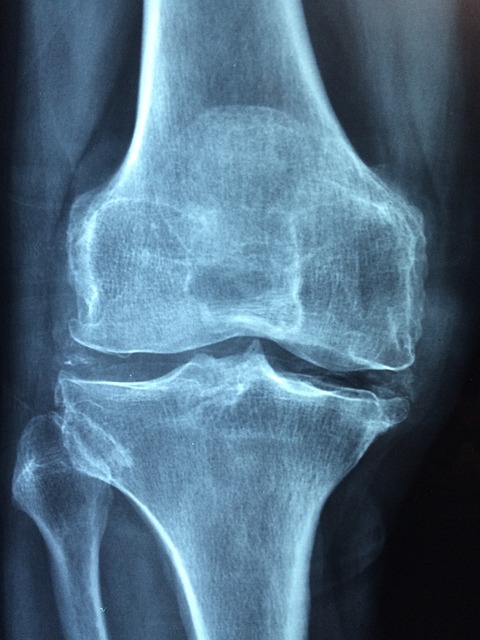

관절염이란?

1. 정의

관절이란 뼈와 뼈가 만나는 부위입니다. 관절은 뼈 사이가 부드럽게 운동하도록 연골이나 인대 등의 구성으로 조직되어있고 움직임이나 충격에 따라 그것을 흡수하는 아주 중요한 역할을 합니다.

이러한 관절에 염증이 생긴 것을 관절염이라고 합니다.

2. 증상

관절염의 증상에는 굉장히 여러 가지가 존재합니다. 아무래도 연골이 있다 보니 나이가 들면 자연스레 약해지기 마련이죠. 그러나 폭발적인 운동을 하는 운동선수나 교통사고 등의 외부 충격이 크게 다가온 사람에게는 관절의 건강이 약해져 있을 수 있죠. 나이에 상관없이 이러한 증상이 있다면 병원에 내원하시는 것을 추천드립니다.